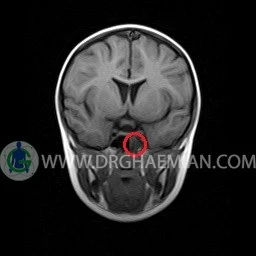

ام آر آی مغز با استفاده آهنربا های قوی و امواج رادیویی تصاویری از مغز و بافت های عصبی پیرامونی آن ایجاد می کند. در این کیس سینوزیت حاد سمت چپ به همراه ماستوئیدیت دیده می شود.

– Mucosal thickening with fluid level in left mastoidal cells suggestive for mastoiditis

– Mucosal thickening with fluid in left sphenoid sinus suggestive for acute sinusitis

are seen